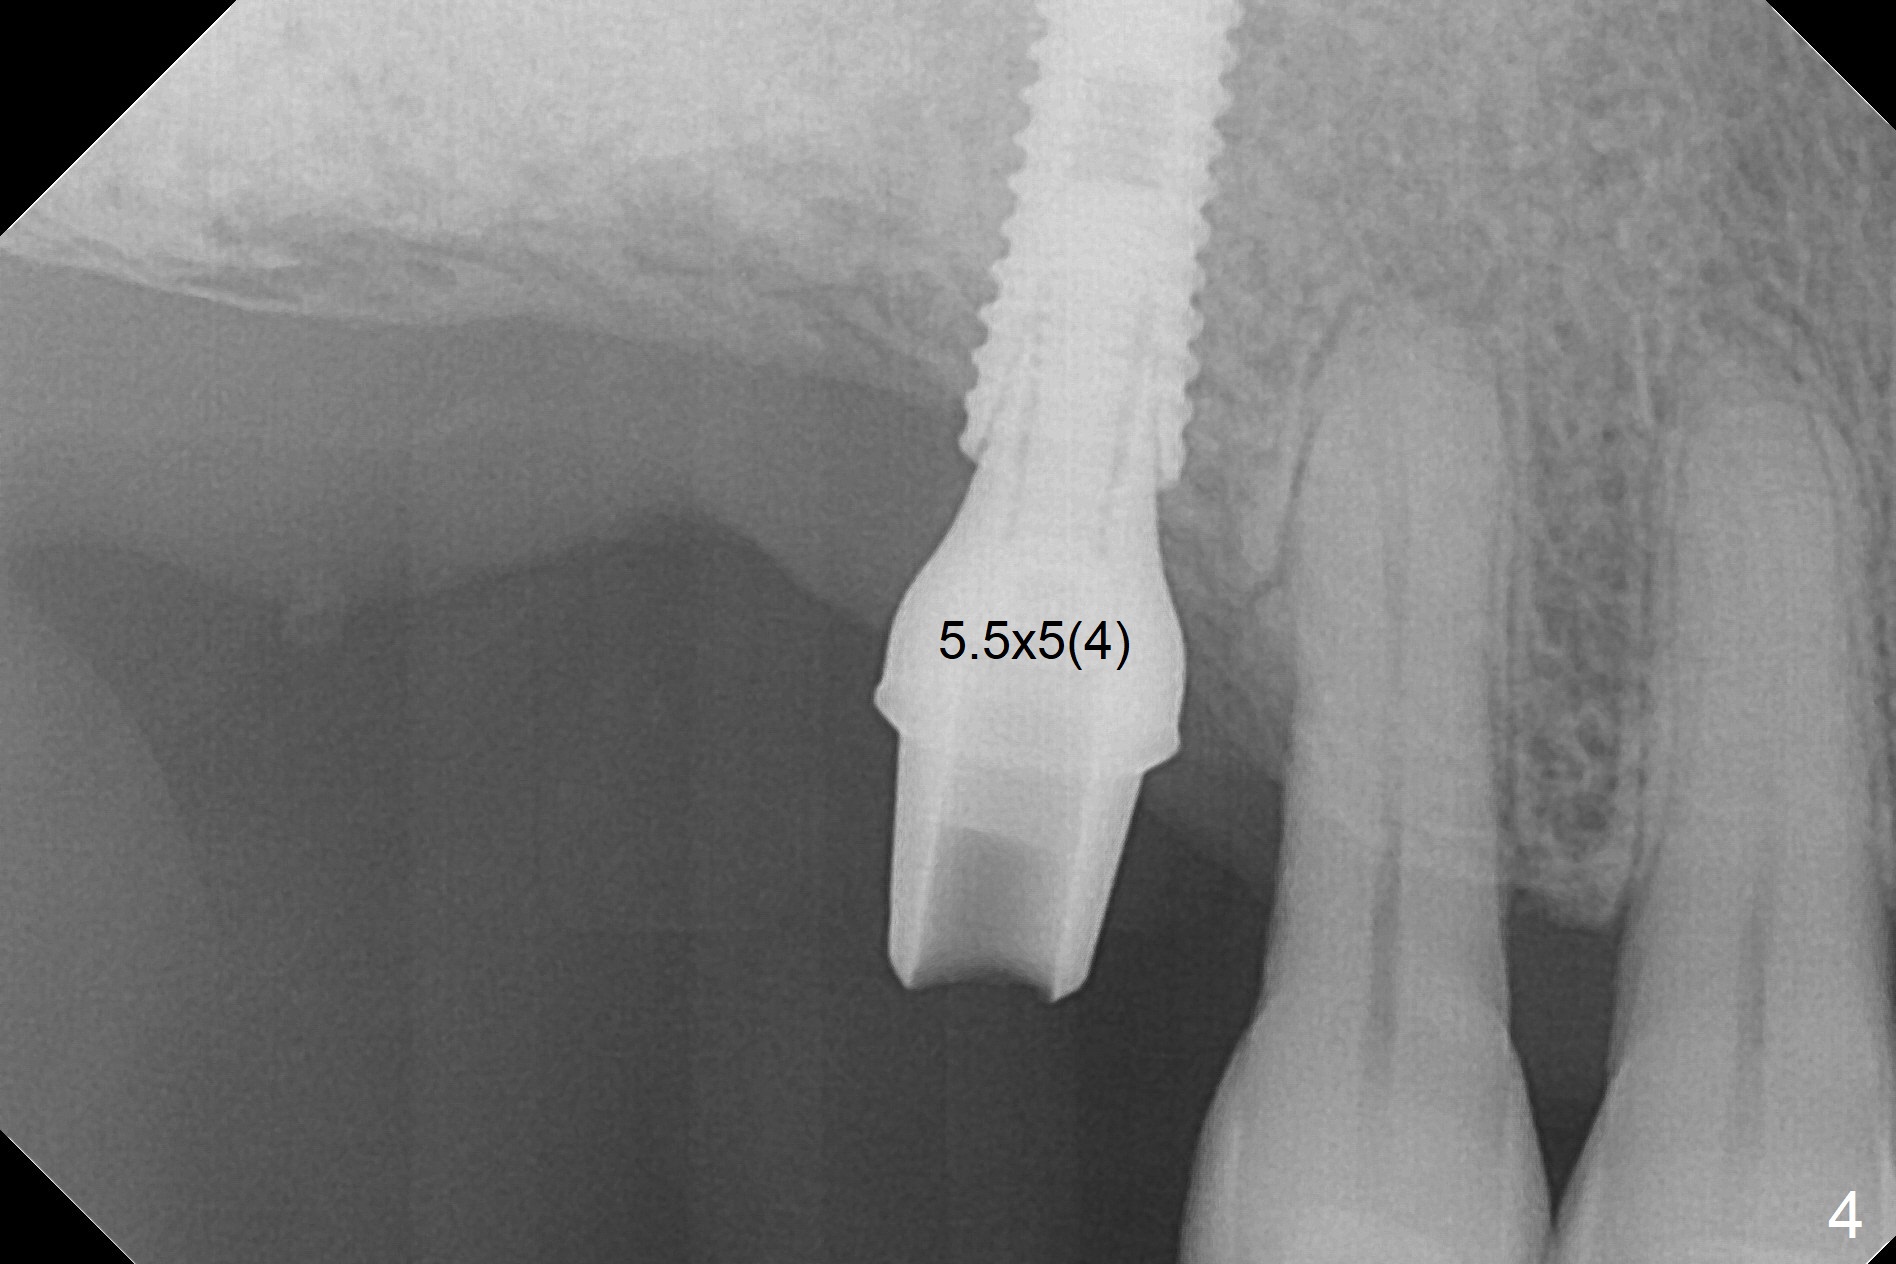

Bone Expansion Alternates with Drill

Since the ridge crest at #3 is narrow, Tatum bone scalpels are used to get access and initiate bone expansion, followed by bone blades and RT 2.  It seems that the osteotomy starts mesially; bone height being increased (Fig.1).  When the apical end of the osteotomy tilts mesially, more bone height is obtained.  Drills are alternatively applied because of the hard bone (Fig.2).  A 4x13 mm UF implant is placed initially with the distal threads unburied (Fig.3, >50 Ncm).  With further seating of the implant, a 5.5x5(4) mm abutment is used (Fig.4), which closes the access.  No suture is warranted.  An immediate provisional is fabricated for the patient's comfort and psychological effect.  In fact, the abutment cuff changes to 5 mm prior to temporarization.  There appears no bone loss <4 months postop (Fig.5).  Pulpitis develops at #4 due to DO caries 1 year 5 months post cementation (Fig.6 *).  The crown at #3 is removed for easy and conservative distal carious removal and Cavit temporary restoration to prevent sodium hypochlorite leakage.  Then occlusal access is made for pulpotomy.  When RCT finishes, no crown will be made, but occlusal reduction is required.    The patient returns for RCT 1 month later (Fig.7,8). Cavit remains in place (Fig.7 C).  Although 2 threads are exposed distal (Fig.8 arrow), there is no sign or symptom of periimplantitis, which may be related to the thick gingiva (arrowhead).  Return to Upper Molar Immediate Implant, IBS, #14 (Tissue Punch) Xin Wei, DDS, PhD, MS 1st edition 08/25/2017, last revision 09/08/2019